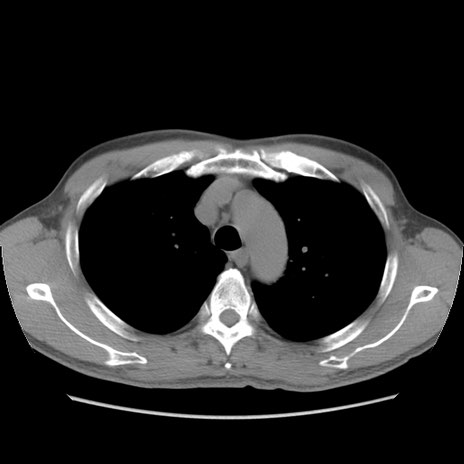

症例56 CT(横断像)